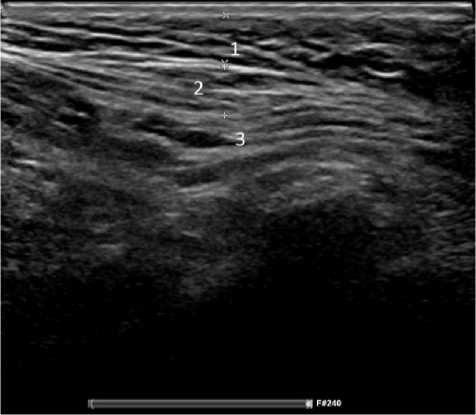

Обследование 242 пациентов показало, что диагностика паховой грыжи у мужчин не сложна. Клинические проявления заболевания позволяли во время осмотра установить диагноз, а при УЗИ оценить состояние тканей в паховых областях, локализацию грыжи (прямая или косая) и определить содержимое грыжевого мешка, что имело значение для установления сроков выполнения операции. У женщин были проблемы ранней диагностики неосложнённой грыжи при астеническом телосложении и у гиперстеников, страдающих ожирением. На ранних сроках развития грыжи женщины предъявляли жалобы на боли в паху при отсутствии над ним опухолевидного образования. При этом из-за особенностей расположения наружного отверстия пахового канала в проекции половых губ определить грыжу при пальцевом исследовании было не всегда возможно. Объяснить эту особенность можно тем, что при косой паховой грыже, спускающейся через глубокое паховое кольцо, грыжевой мешок расслаивает круглую связку матки, имеющей малый диаметр, не выходит за её размеры. При прямой паховой грыже грыжевой мешок смещается параллельно круглой связке матки, подходит к наружному паховому кольцу и располагается под ним в виде опухолевидного образования, что позволяет клинически поставить диагноз. У пациенток с ожирением из-за избытка жировой ткани в надлобковой области определить грыжевой мешок при отсутствии клиники ущемления, выходящий из наружного отверстия пахового канала, практически очень сложно, что для установления диагноза требует применения инструментальных методов исследования. Применение УЗИ позволяло установить и подтвердить диагноз у пациентов с паховой грыжей. На рисунках 1 и 2 представлены результаты УЗИ у пациента Н., 37 лет, с двухсторонней паховой грыжей, которые позволили подтвердить диагноз и выполнить операции по поводу паховых грыж открытым способом с двух сторон. На рисунке 3 представлены результаты УЗИ пациентки Н., 45 лет; диагноз – правосторонняя косая паховая грыжа: вид грыжевого мешка, расположенного в круглой связке матке.

Рисунок 2. Пациент Н, 54 года. Изображение прямой правосторонней паховой грыжи при ультрасонографическом исследовании: 1 — подкожно-жировая клетчатка; 2 — наружная косая мышца живота; 3 — грыжевой мешок

Figure 2. Patient H., 54 years old. Ultrasonographic image of a direct right-sided inguinal hernia: 1 – subcutaneous fat; 2 – external oblique abdominal muscle; 3 – hernial sac